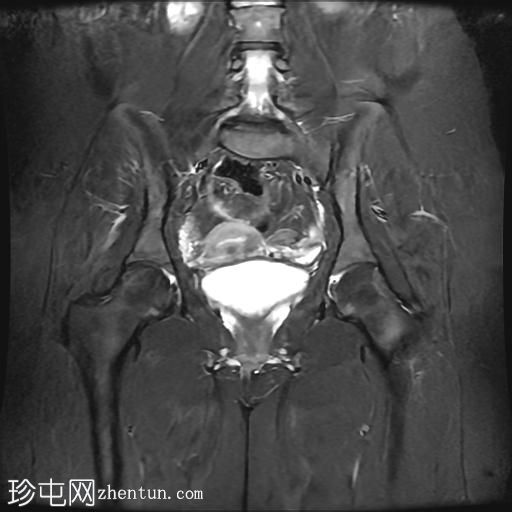

MRI

矢状位

T2加权像

脂肪抑制像

冠状位T2加权像

臀中肌髂骨起点处前侧全层撕裂,伴有充满液体的间隙,以及髂骨髓水肿。

MRI结果符合臀中肌近端髂骨起点处全层撕裂的

影像

学表现。